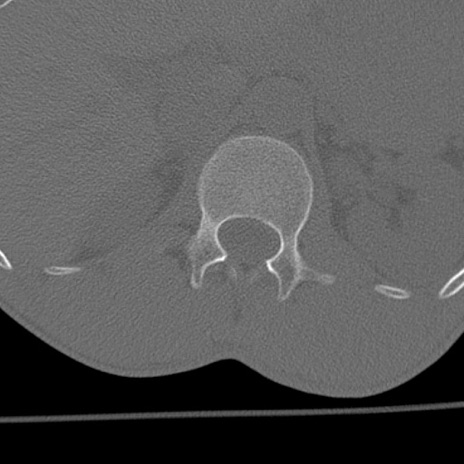

症例3 腰椎CT(横断像)

腰椎CT